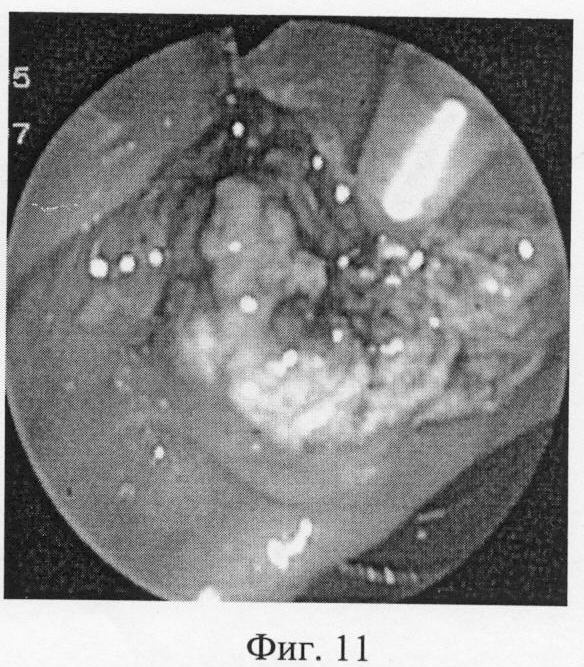

На эндоскопических фотографиях (фиг.6-12) наглядно представлены этапы операции эндоскопической папиллотомии предложенным новым нетипичным способом – крестообразным разрезом.

Фиг.11 – дополнительный поперечный разрез трубчатой структуры в глубине раны.